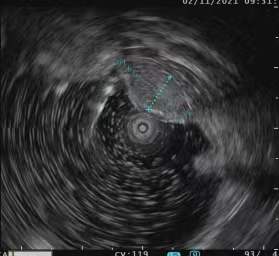

超声微探头通过钳道对病灶进行超声检查超声内镜的应用1、消化道黏膜下病变的诊断

通常消化道可以分为5层,从内到外依次为粘膜层、粘膜肌层、粘膜下层、固有肌层、浆膜层。由于胃镜和肠镜是肉眼可见光成像,只能看到消化道最表面的一层(粘膜层)。然而有些病变来源于粘膜下,此时普通胃肠镜就不能透过粘膜对粘膜下的病变做出诊断;还有些病变位于胃腔外紧贴胃壁,普通胃肠镜更是难以诊断。超声内镜将内镜和超声的功能结合在一起,能更好地对粘膜下结构或病变进行观察和判断

。

胃体粘膜下脂肪瘤